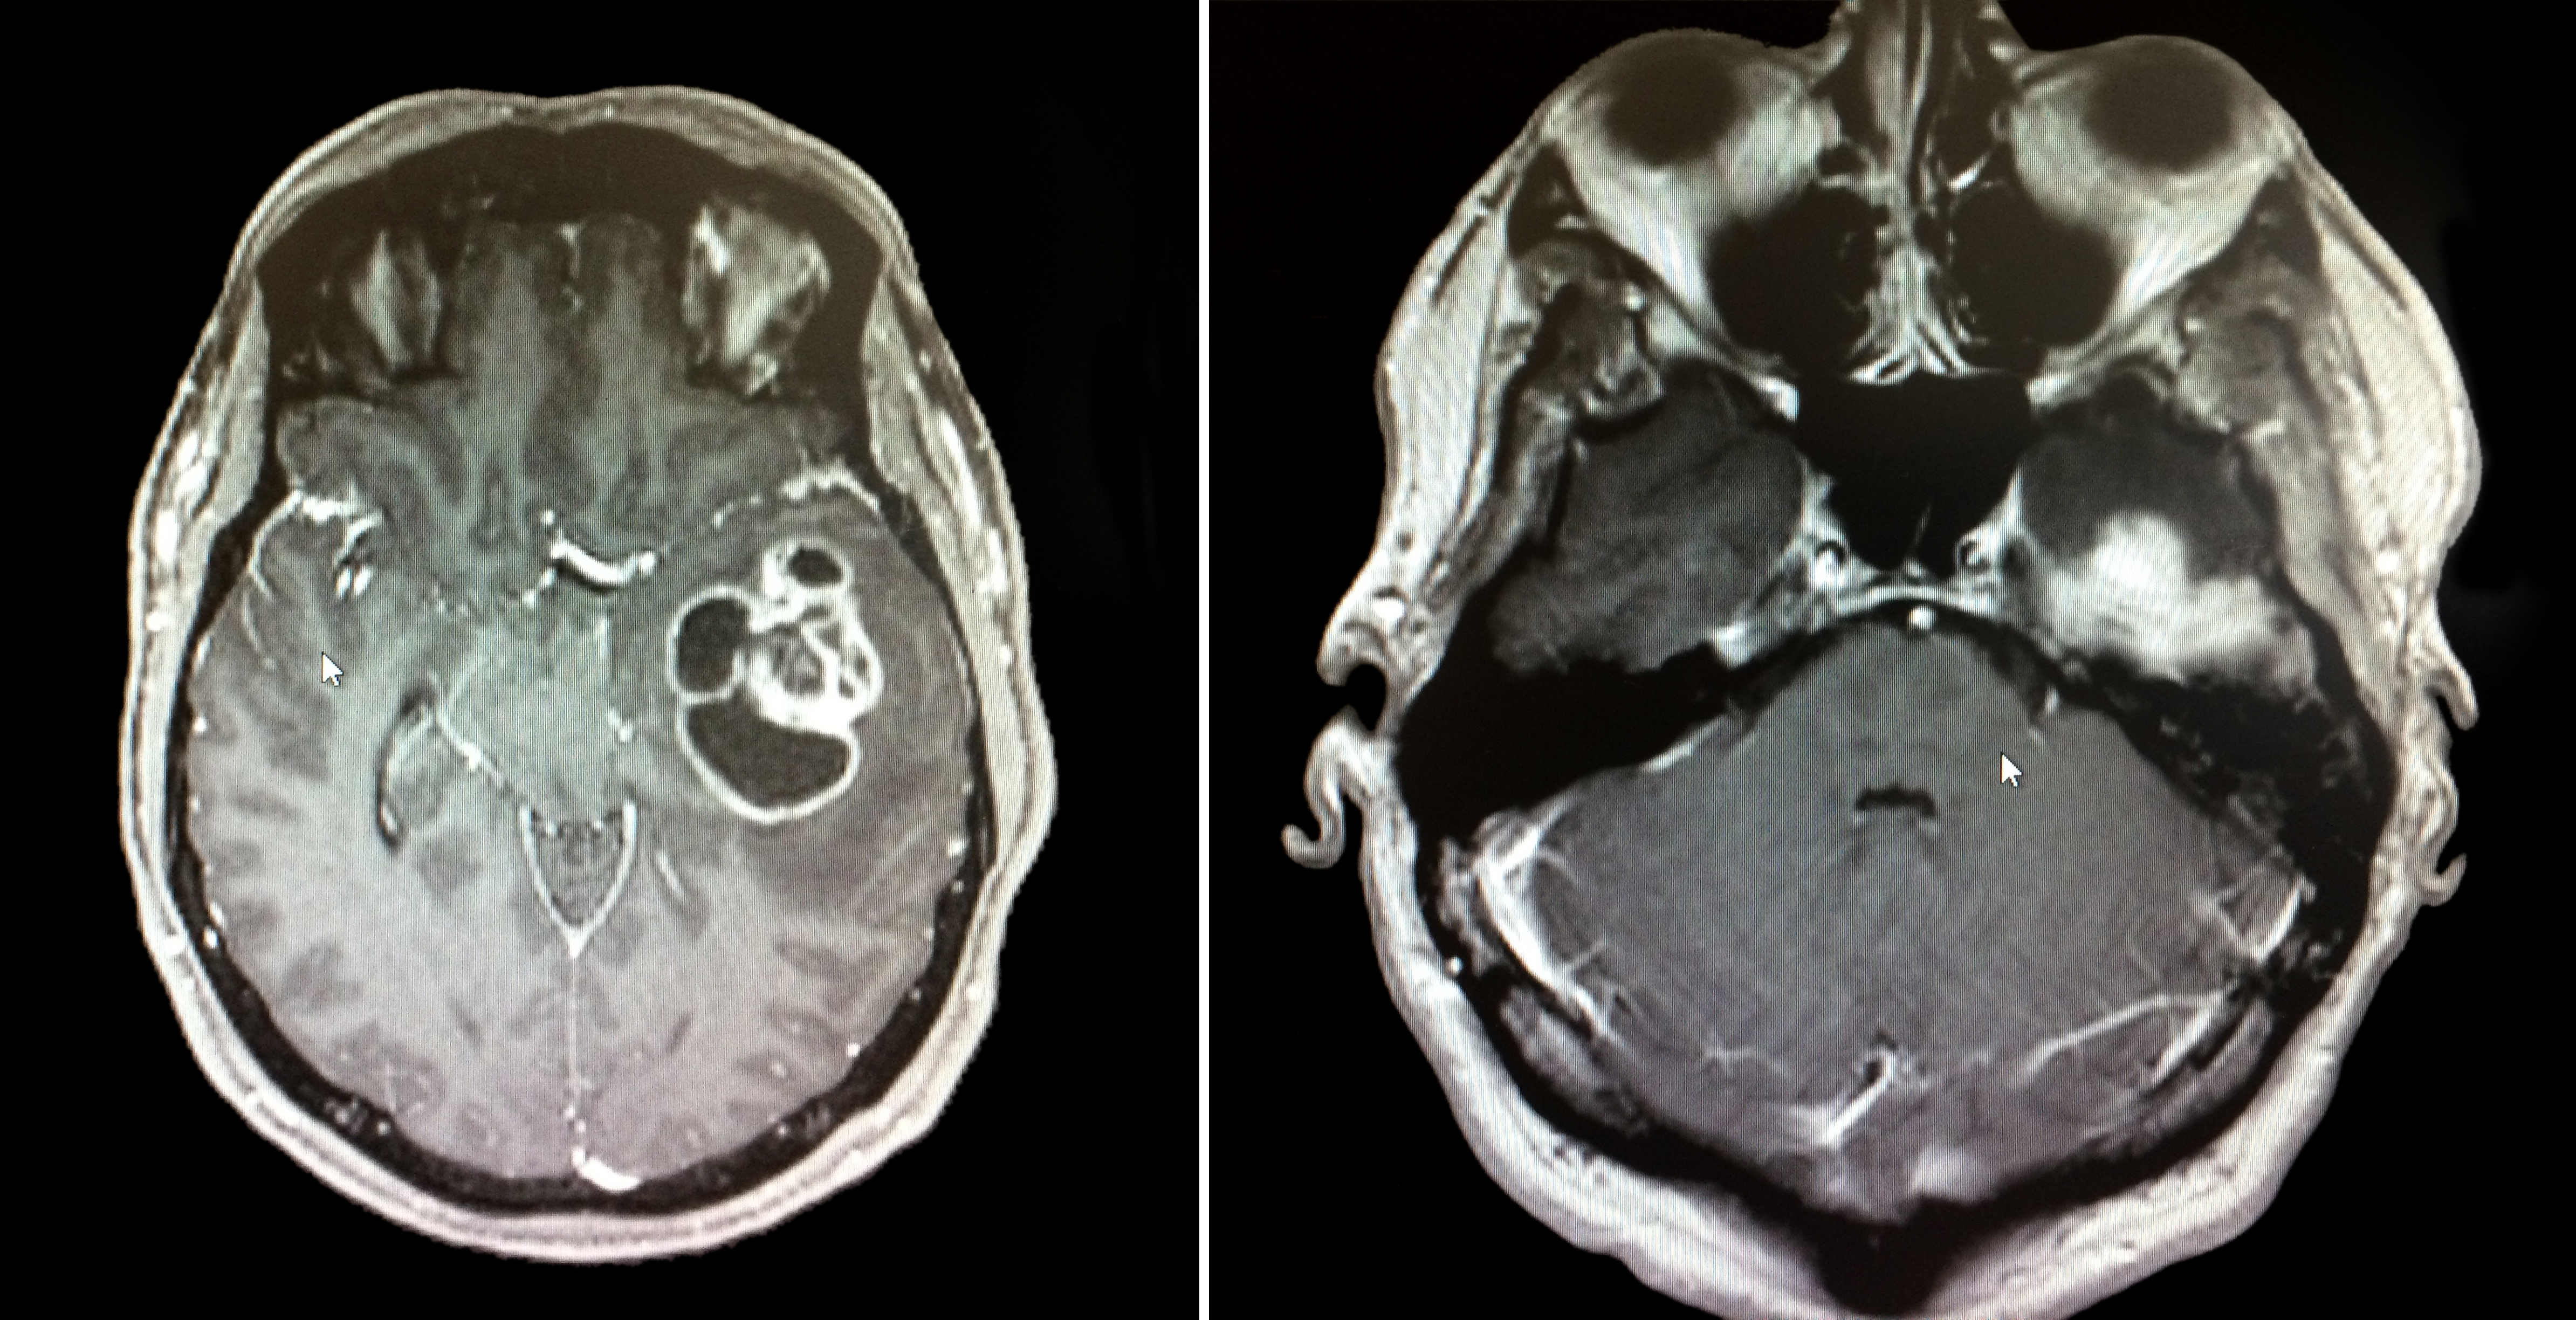

Three dimensional culture systems and patient derived cells successfully allow for tumoroid development. Tumoroids are structures that grow and appear morphologically similar to naturally growing tumors in a patient. Tumoroids show promise for testing new drugs and cancer treatments. For instance, glioblastoma is a form of brain cancer that is aggressive, fast growing, and deadly. In particular, the mesenchymal subtype of this cancer shows more proliferative growth in a faster period of time. To better understand the tumoroid development, Dr. Lisa Oliver and her research team have created a 3D cell culture model, which mimics the environment in which glioblastoma and mesenchymal tumor cells grow.

To mimic the tumor microenvironment found in the brain, a co-cell culture was made using patient derived cells and bone marrow mesenchymal stem cells. A co-culture refers to a cell culture that contains two or more types of cells. The patient derived cells were collected from patients that were undergoing glioblastoma tumor removal surgery. The stem cells were collected from a French tumor library. The cell viability, cell proliferation, and percentage of tumor-initiating cells was analysed for the growing tumoroids. The morphology of the tumoroids, such as their length, area, and circularity, were analyzed. Additionally, radiation and chemotherapy were used on these tumoroids to determine their survival and cell proliferation probabilities.

The researchers noticed that patient derived cells began to create multicellular spheroids within seven days of being placed in the co-culture. It was inferred that the tumoroids responded to radiation methods, as there was a decrease in the number of cells in the culture. In addition, the morphology and behavior of the lab-grown tumors exhibited similar characteristics to patient-related glioblastoma and mesenchymal tumors.